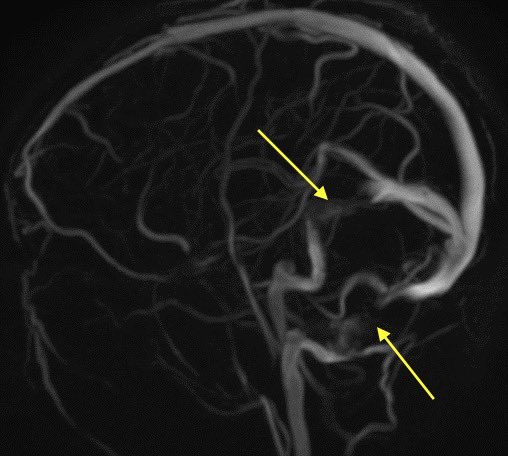

2️⃣Tortuous optic nerves and intraocular protrusion: again, increased pressure leads to protrusion, tortuous nerves, and prominent CSF surrounding the nerves within the sheath